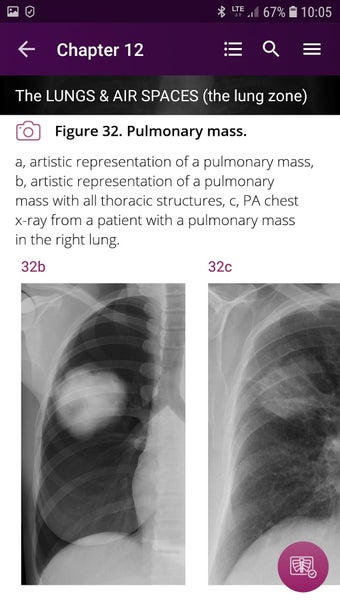

Radioloji'yi Keşfet: Göğüs Röntgeni Yorumlama, göğüs röntgeninin yorumlanmasının anlaşılmasını artırmak için tasarlanmış bir eğitim uygulamasıdır ve doktorlar, tıp öğrencileri ve radyologlar tarafından kullanılması amaçlanmaktadır. Uygulama, en küçük detayları görüntülemek için yakınlaştırılabilecek yüksek kaliteli görüntüler ve her bulgunun önemini anlamanıza yardımcı olacak bir sesli yorum içerir.

Uygulamanın amacı, kullanıcıların farklı x-ışını bulgularını ve bunların bir hastalığın teşhisinde nasıl kullanılabileceğini daha iyi anlamalarına yardımcı olmaktır. Uygulama, göğüs röntgeni yorumlaması için gerekli çeşitli yapı taşlarını kapsayan 5 bölüme ayrılmıştır.

Ayrıca, uygulama bir hastanın göğüs röntgenini incelemeleri sırasında başvurabilecekleri bir dizi nasıl yapılır içerir. Uygulamadaki nasıl yapılır adımlarını takip ederek, kullanıcılar birçok farklı bulguyu doğru bir şekilde tanımlayabilecekler ve her birini bir hastalığın teşhisi için nasıl doğru bir şekilde kullanacaklarını öğrenebileceklerdir.